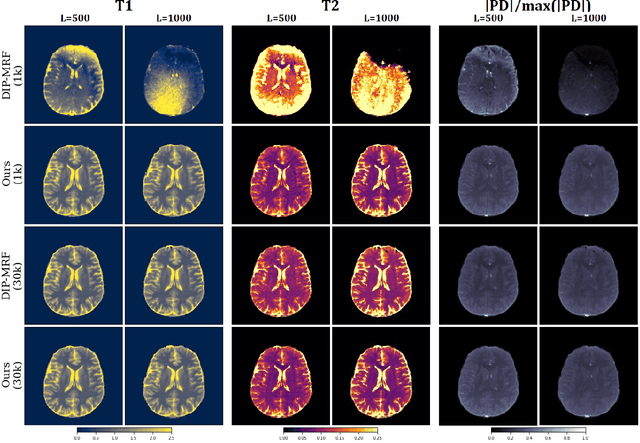

The estimation of multi-parametric quantitative maps from Magnetic Resonance Fingerprinting (MRF) compressed sampled acquisitions, albeit successful, remains a challenge due to the high underspampling rate and artifacts naturally occuring during image reconstruction. Whilst state-of-the-art DL methods can successfully address the task, to fully exploit their capabilities they often require training on a paired dataset, in an area where ground truth is seldom available. In this work, we propose a method that combines a deep image prior (DIP) module that, without ground truth and in conjunction with a Bloch consistency enforcing autoencoder, can tackle the problem, resulting in a method faster and of equivalent or better accuracy than DIP-MRF.